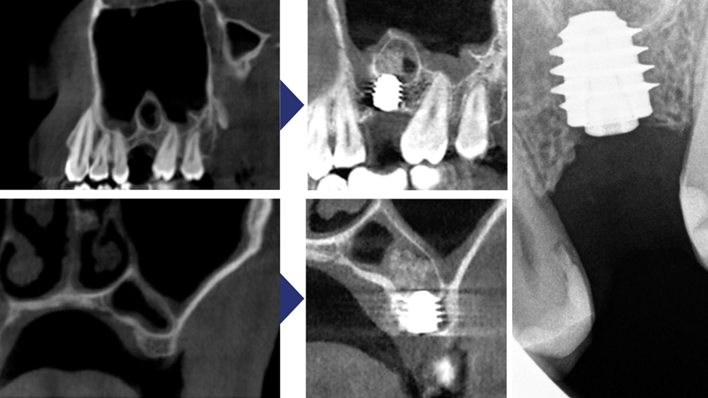

Klinikinis atvejis: Vėlyvoji implantacija: viršutinio žandikaulio ančio dugno elevacija, implanto sriegimas ir kraštinė kaulo regeneracija;

- Dr. Irfan Abas klinikinis atvejis -

Raktažodžiai:

Vėlyvoji implantacija, ančio dugno elevacija, ančio dugno elevacija atviru būdu, kraštinė kaulo regeneracija, Dr. Irfan Abas, AnyRidge, MiLA chirurginis rinkinys, kaulo regeneracija;

Produktai:

AnyRidge implantų sistema, MILA chirurginis rinkinys;